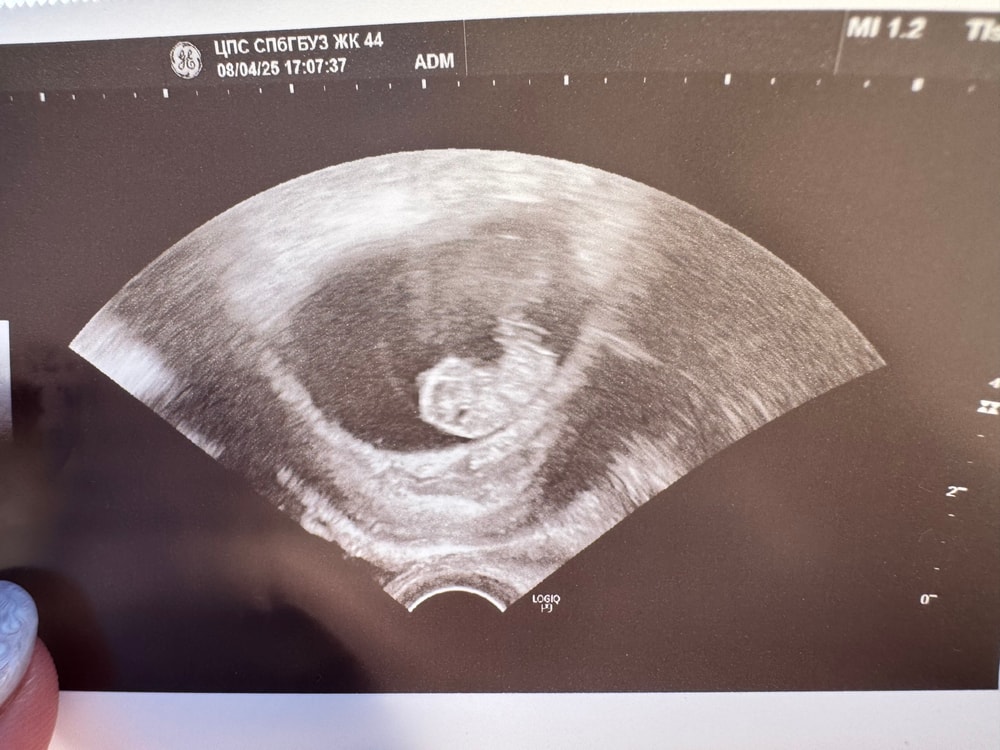

Всем привет , все хорошо , сердце бьется ,человек растет 😁 следующее узи 8.04.25 и на учет вставать.